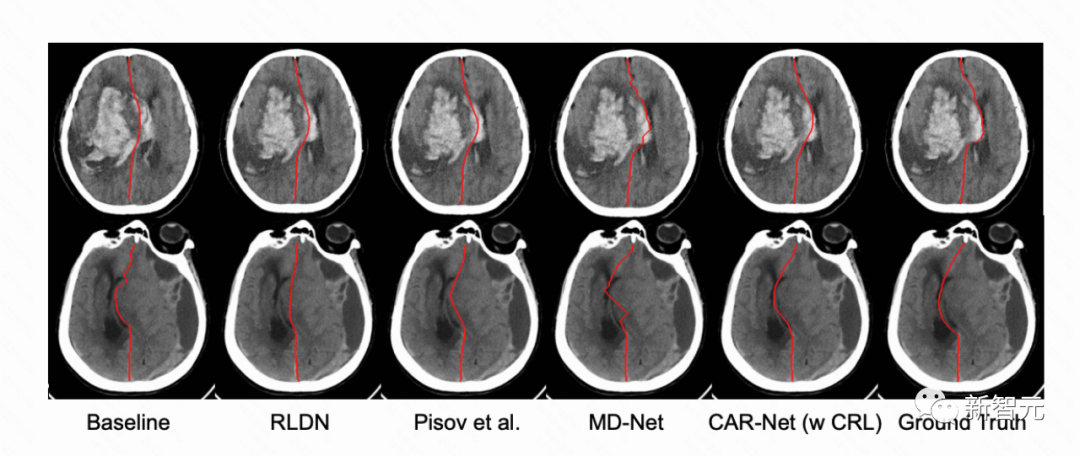

(机器学习自动勾勒脑中线产品,王哲跟团队提出的方法发表在医疗影像领域顶会MICCAI)